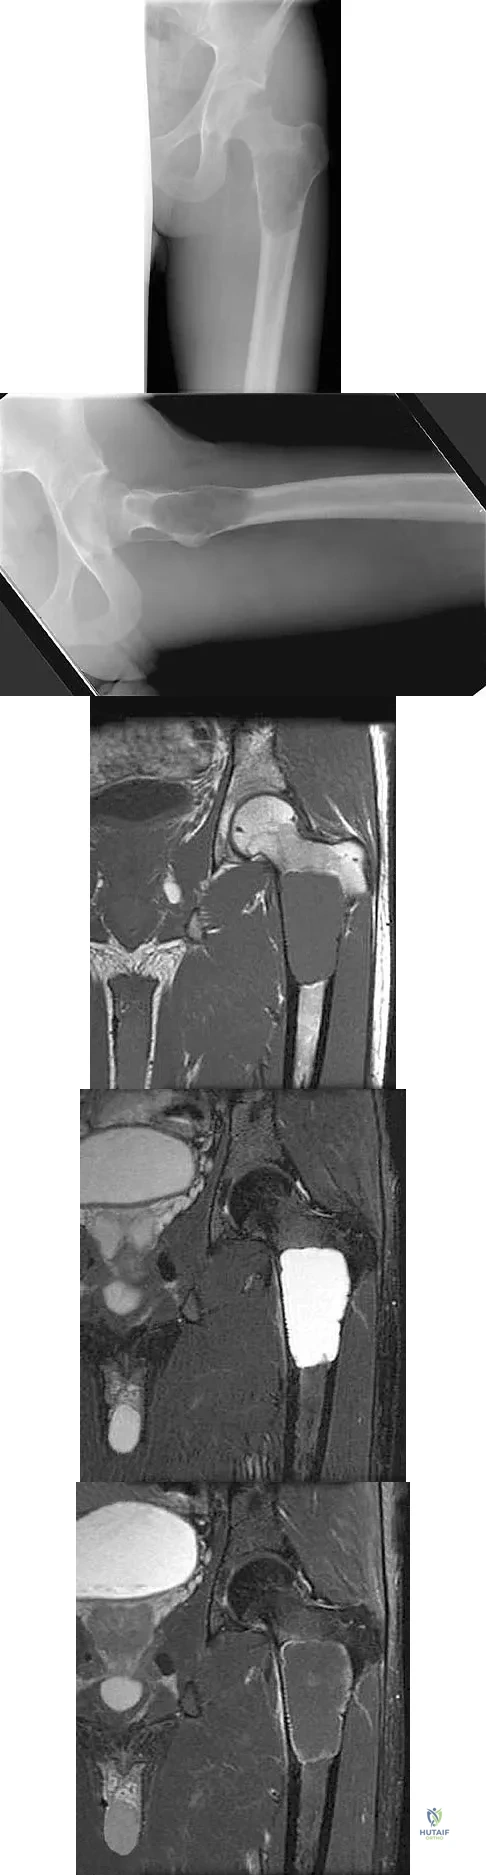

Question 77

A 68-year-old man reports a 4-week history of progressive left-sided lower back and hip pain. The pain is in the posterior buttock region with radiation to the groin and to the left anterior knee region. The pain is aggravated with walking and improves with rest. There is no history of previous trauma. Radiographs are seen in Figures 14a and 14b, and MRI scans are seen in Figures 14c through 14e. What is the most appropriate treatment option at this time?

Explanation